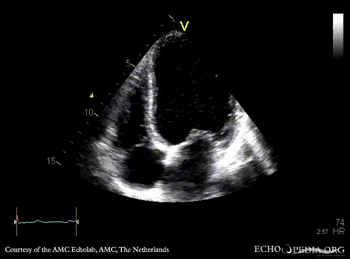

Case 95

Apical and anteroseptal infarction

A4CH: dilated left ventricle, poor function, akinesia of the apex and all midsegments A2CH